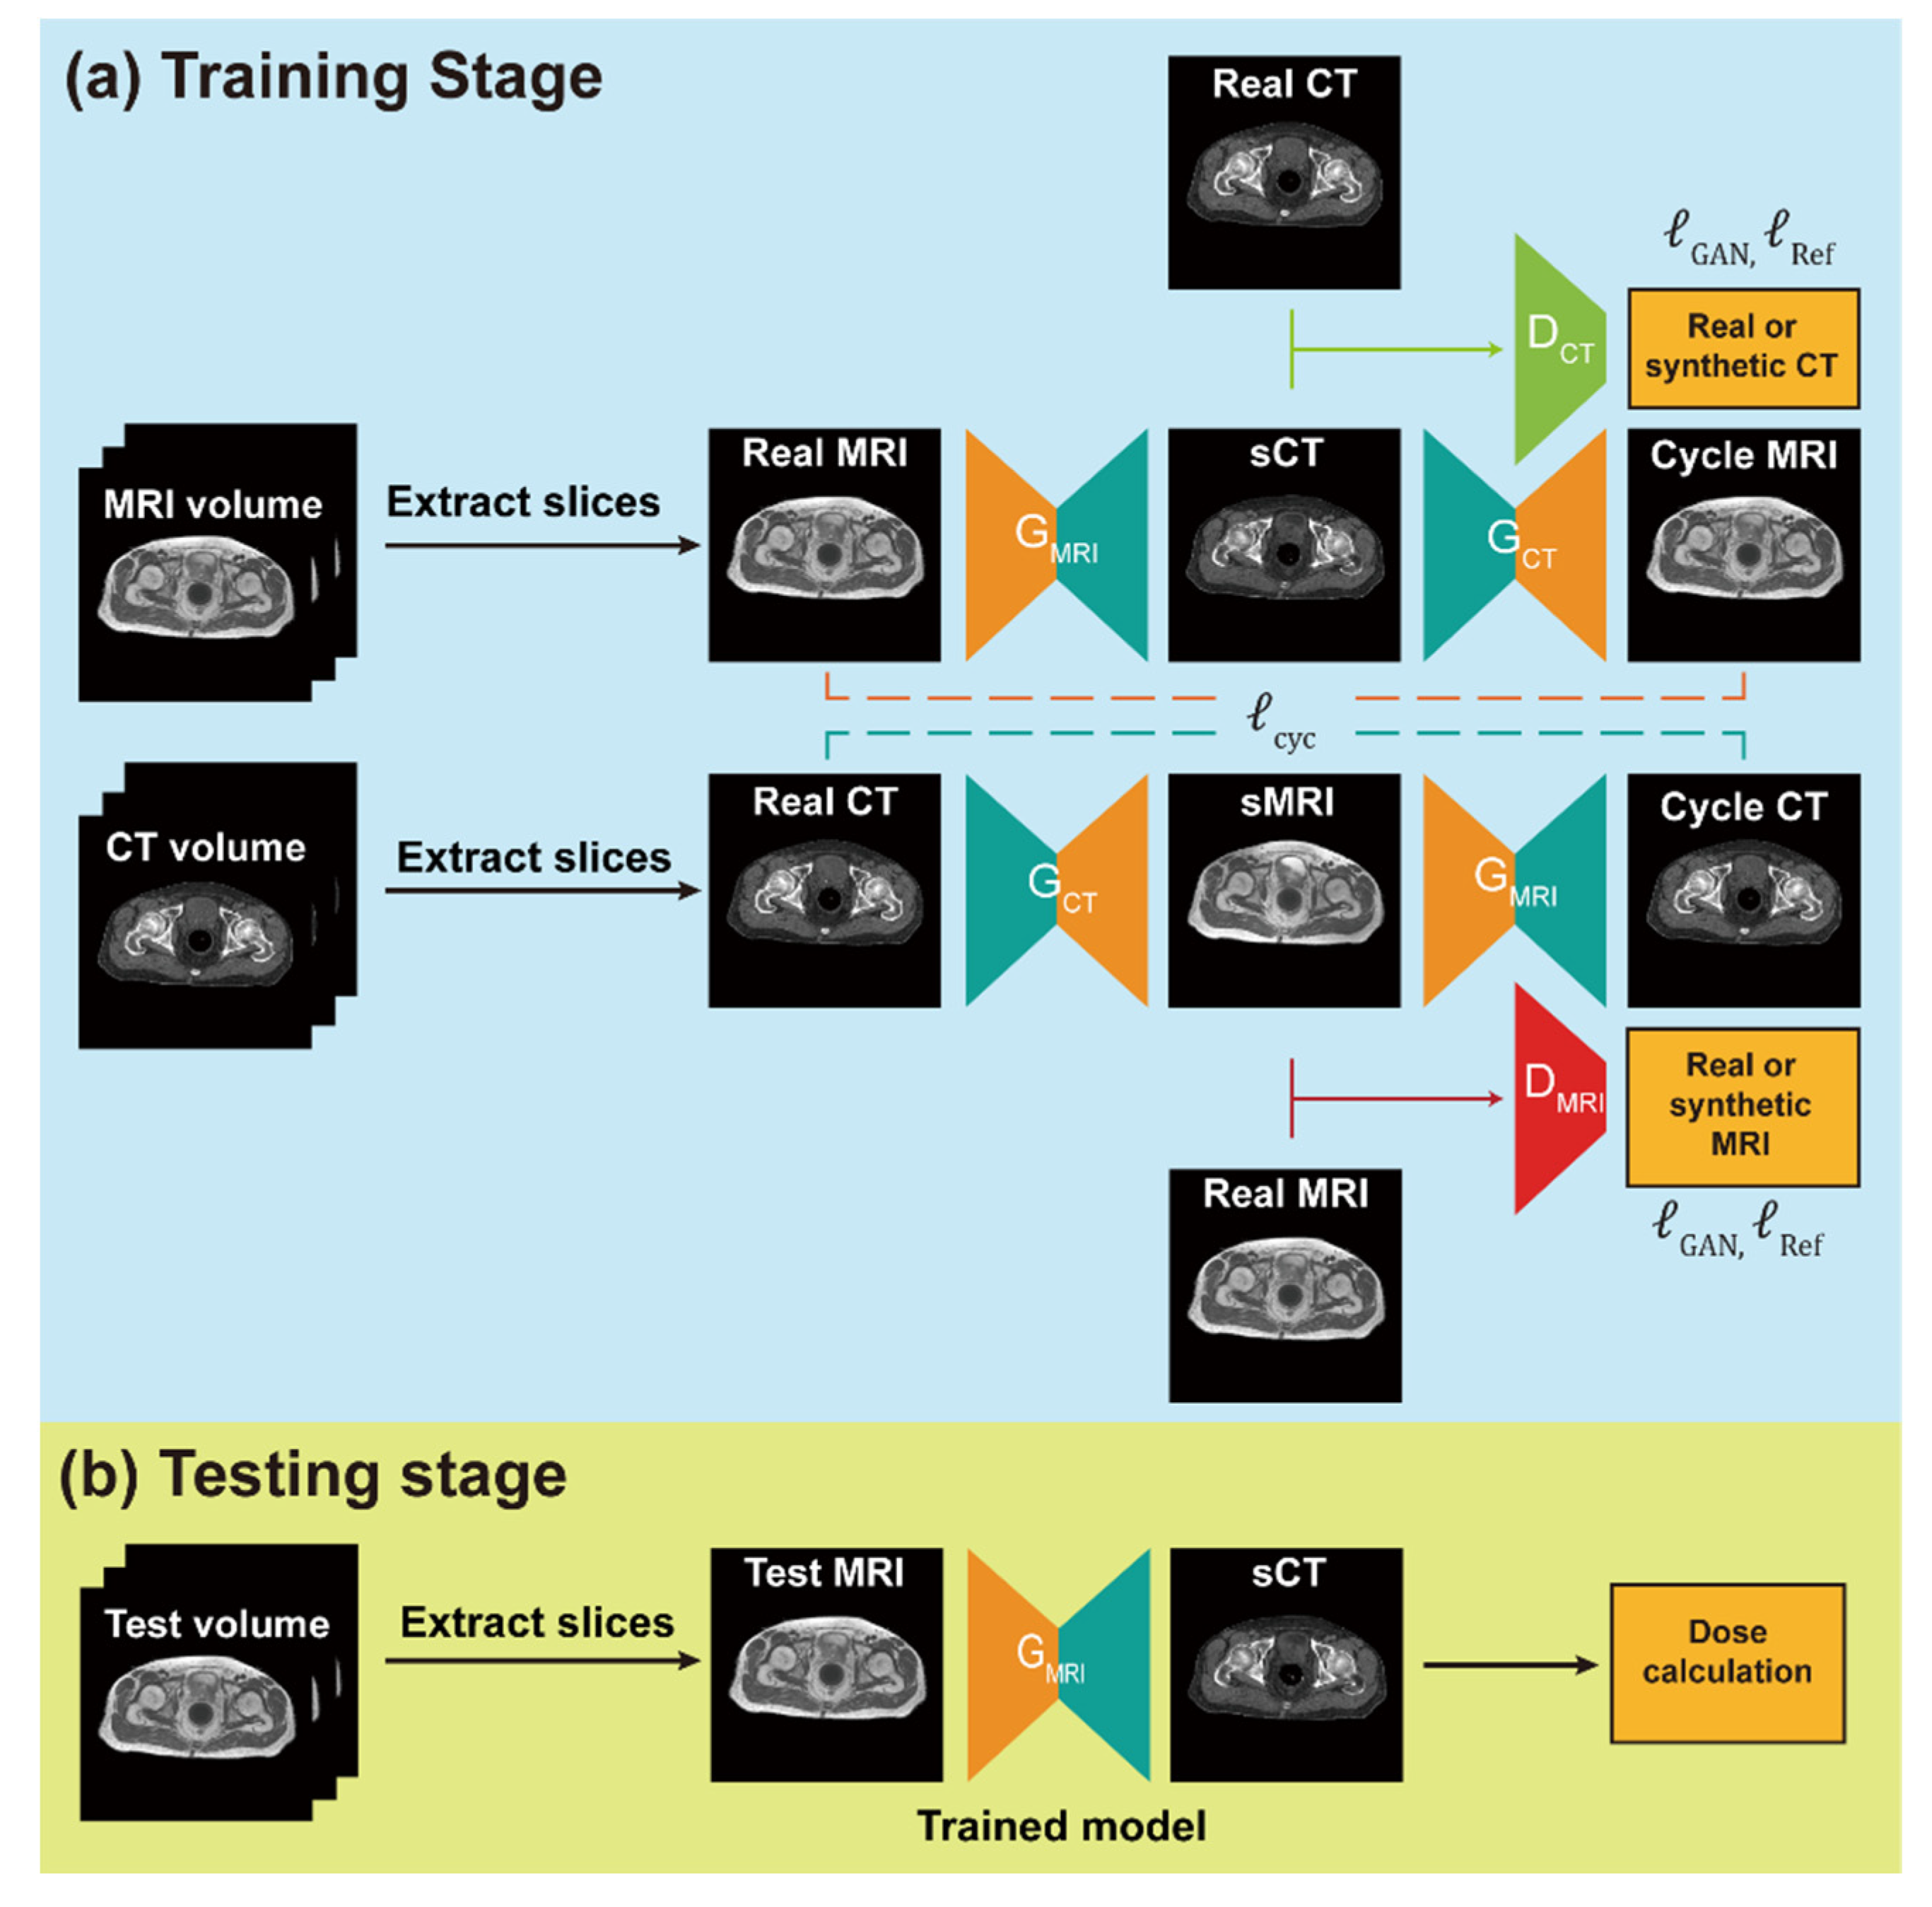

2.3. Network Training and sCT Generation

2.5. Network Training and sCT Generation